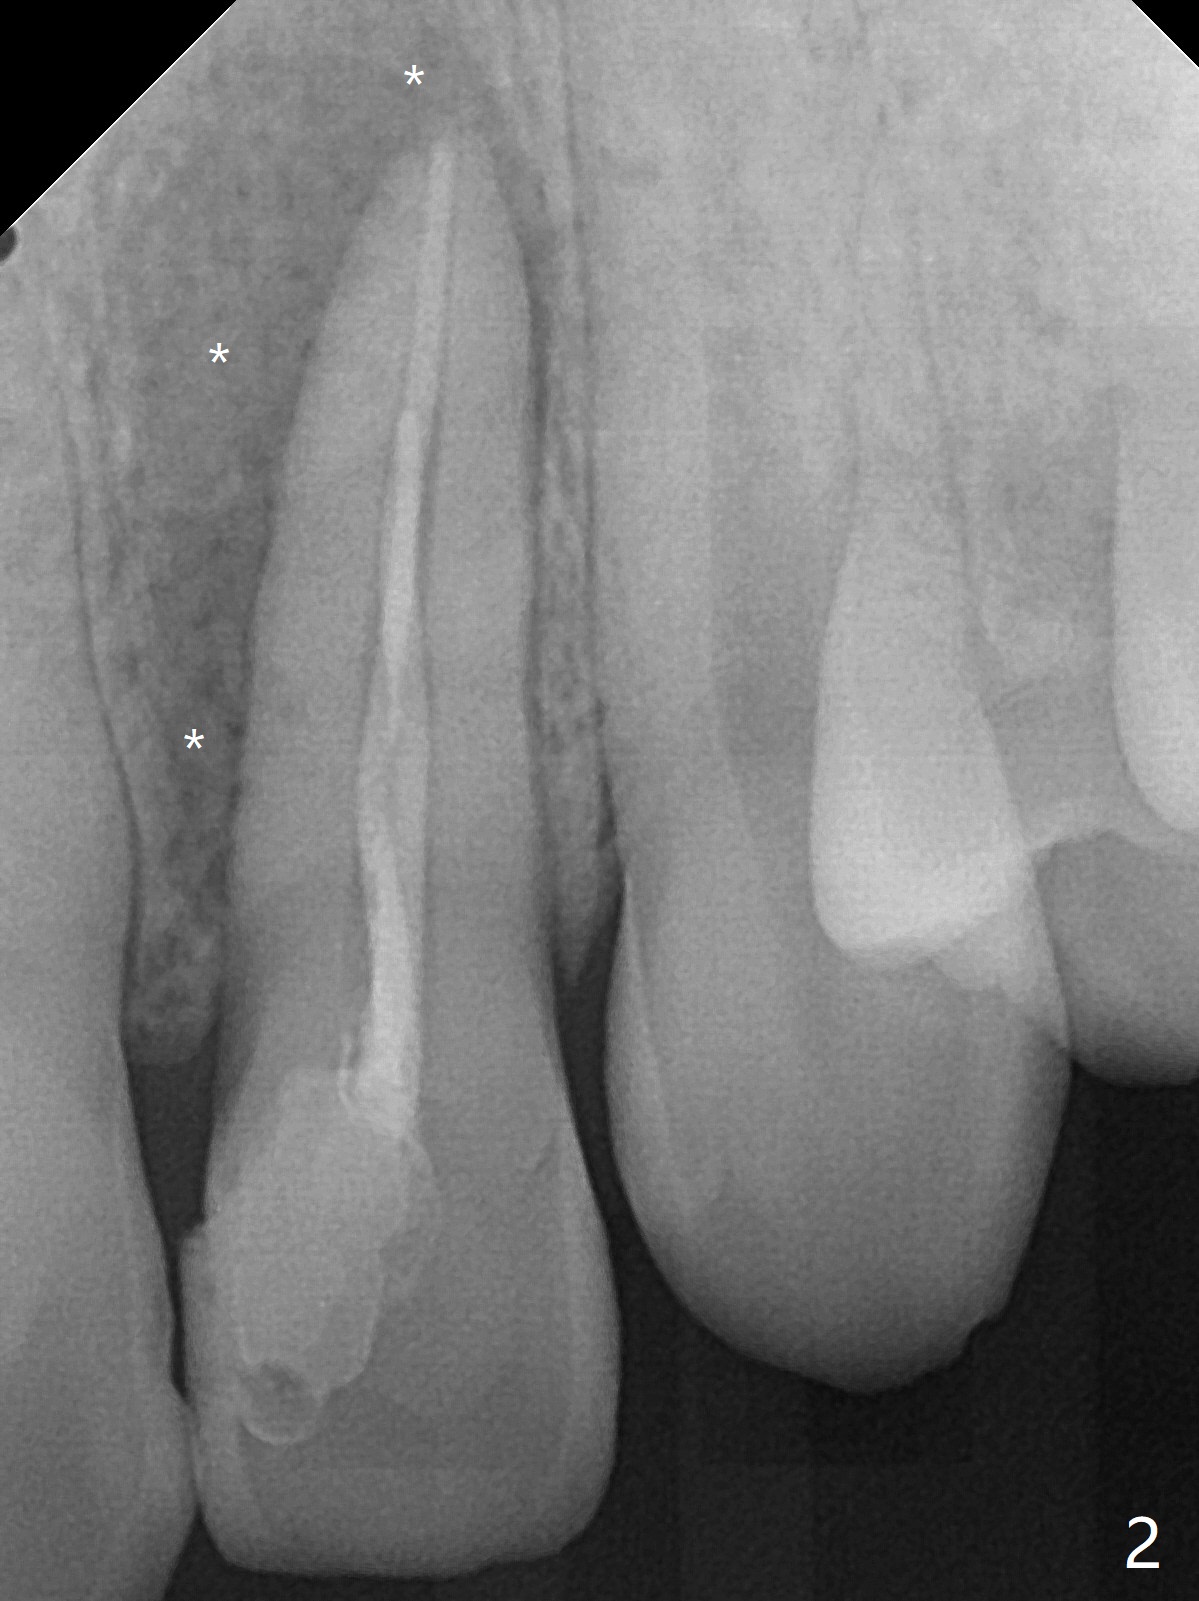

21岁女左上侧切牙根管治疗在别的诊所完成后出现瘘道(图一),近中阴影相当大(图二),应该如何处理?单独重做根管治疗足够吗?牙齿似乎没有松动,牙周袋正常,龋齿易感性高。牙列完整,仿佛没有咬合创伤迹象。可能由于经济问题,家长迟迟不带她去看专家。上个月我开始重做(图三:40/.04),能一次完成治疗吗?保险起见,放置氢氧化钙糊剂(图四)。一个月后病人回来,瘘道减小(图五),多次根管冲洗后,放置主牙胶尖(图六:40/.04),我当时在想根侧方阴影这么大,是不是有侧枝根管?如果扩根完善,根充时可能显示!是吗?其实这是最后根尖片(图七),40/.04主牙胶尖加三个fine, fine accessory gutta percha,并没有显示侧枝根管。